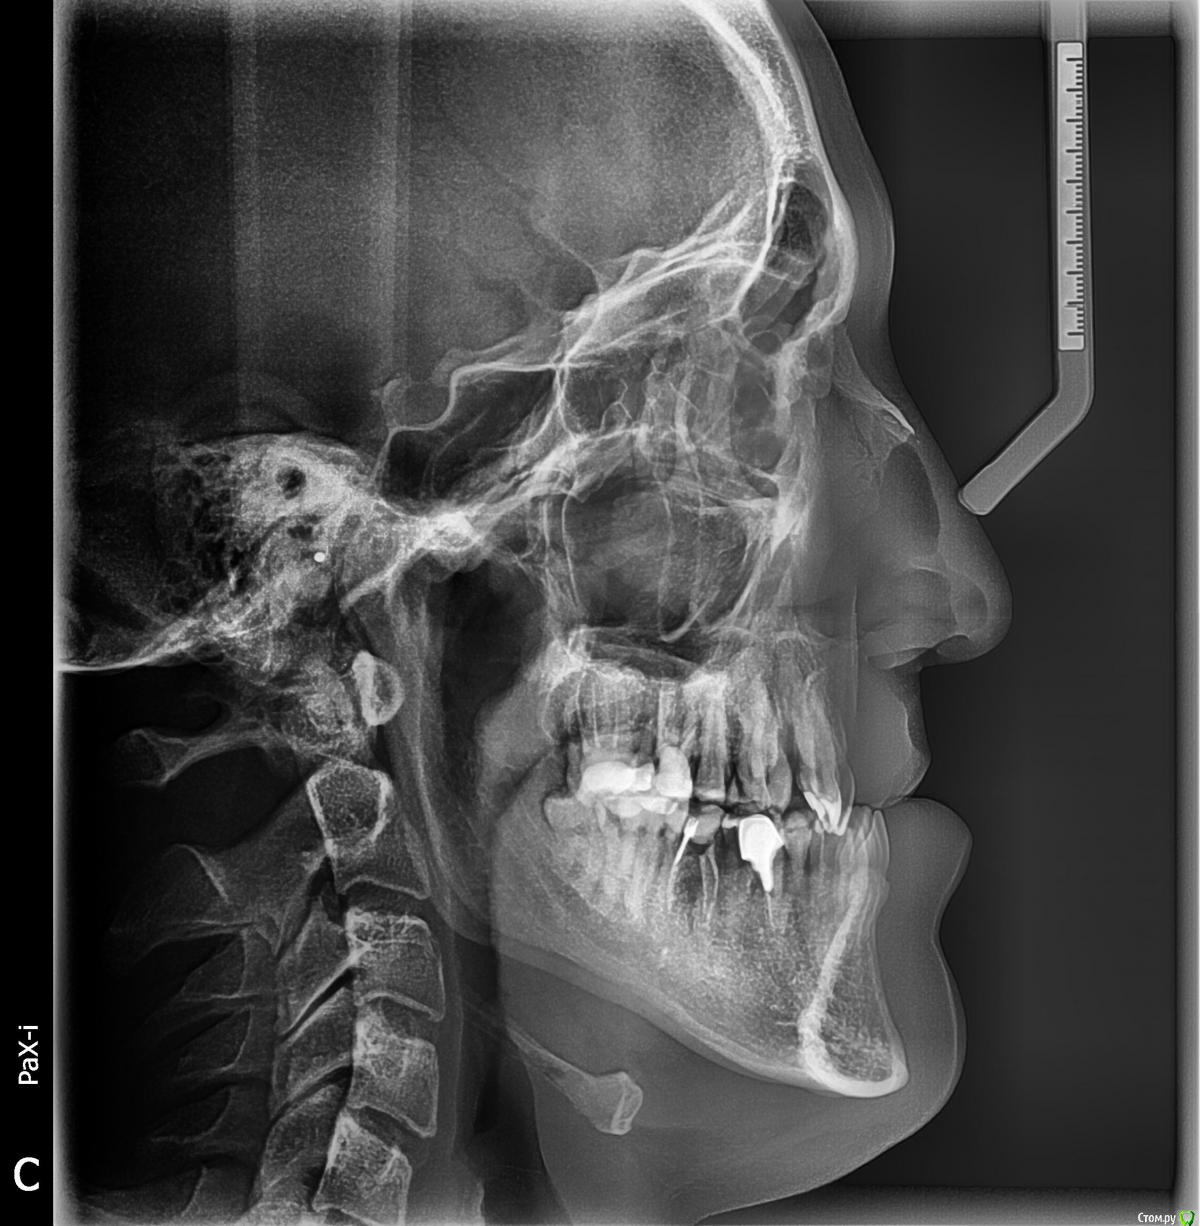

pickuper Опубликовано 5 января, 2018 Поделиться Опубликовано 5 января, 2018 Узкая ВЧ, в детстве стояла специальная пластинка для расширения челюсти, значительного результата это не дало. Потом в силу разных причин лечение забросил.Сейчас 25 лет, поставлен диагноз - верхняя ретромикрогнатия, нижняя прогнатия. Челюстно лицевой хирург, совместно с ортодонтом предлагают следующий план лечения.1) лечение у ортодонта, установка брекетов на верхнею и нижнею челюсть2) горизонтальная дистракция ВЧ3) фронтальная дистракция ВЧ по ФОР 1 или 24) операция Дель Понта на НЧ Ссылка на комментарий

pickuper Опубликовано 5 января, 2018 Автор Поделиться Опубликовано 5 января, 2018 Правильно ли составлен план лечения? И так ли необходима дистракция во фронтальной плоскости, и что еще более интересует для чего нужна операция на нижней челюсти? Ссылка на комментарий

Brigita Опубликовано 6 января, 2018 Поделиться Опубликовано 6 января, 2018 План составлен верно. Как правило операция на верхней челюсти одномоментно проводится, одна, это и ле-фор и дистракция, может что то не так поняли. Ссылка на комментарий

Brigita Опубликовано 6 января, 2018 Поделиться Опубликовано 6 января, 2018 План составлен верно. Как правило операция на верхней челюсти одномоментно проводится, одна, это и ле-фор и дистракция, может что то не так поняли.Согласно поставленному диагнозу и трг.А что не понятно с нижней челюстью? Ссылка на комментарий